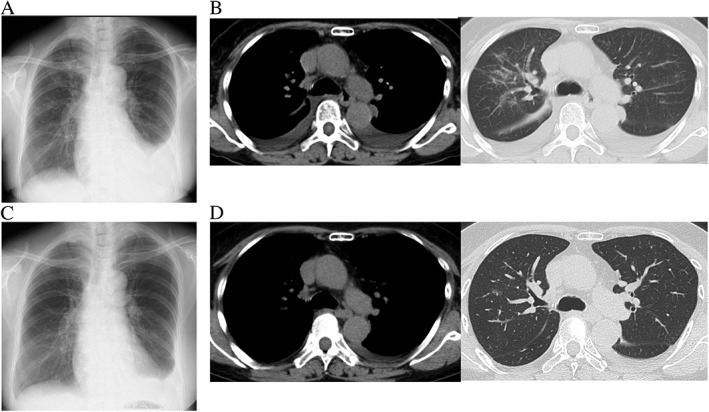

,胸部x片显示右肺野弥漫磨玻璃样影和左侧积液(图1A)。胸部计算机断层扫描(CT)显示双侧胸腔积液增加,右肺野出现新的磨玻璃样混浊(图1B)。

图1(A)胸部X光片显示右肺野弥漫性磨玻璃样混浊和左侧积液。(B)CT显示右肺野有磨玻璃样混浊及双侧胸腔积液。(C和D)类固醇治疗后的胸片和胸部CT图像:双侧胸腔积液和磨玻璃样混浊减少。

明确诊断后,予以泼尼松

25 mg治疗,胸腔积液和磨玻璃混浊立即改善,如图所示(图1C和D)。